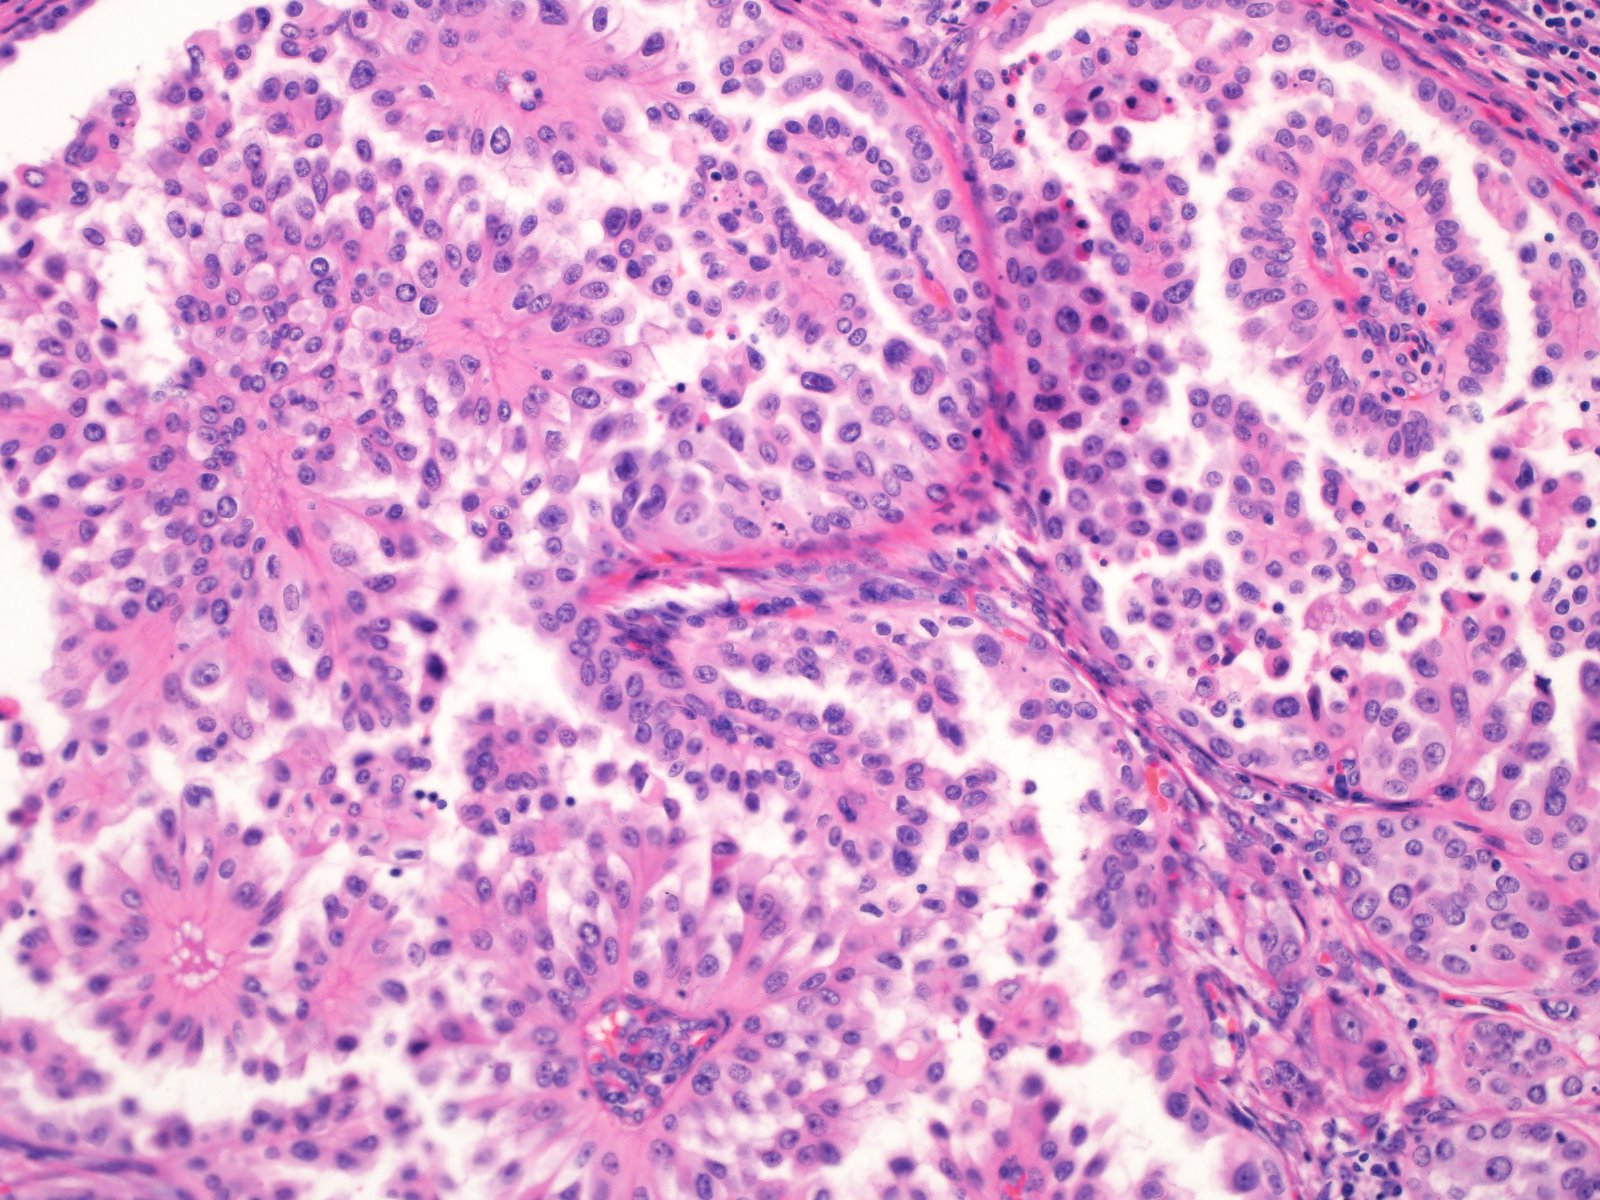

Renal tumor grading

Case ID: 839